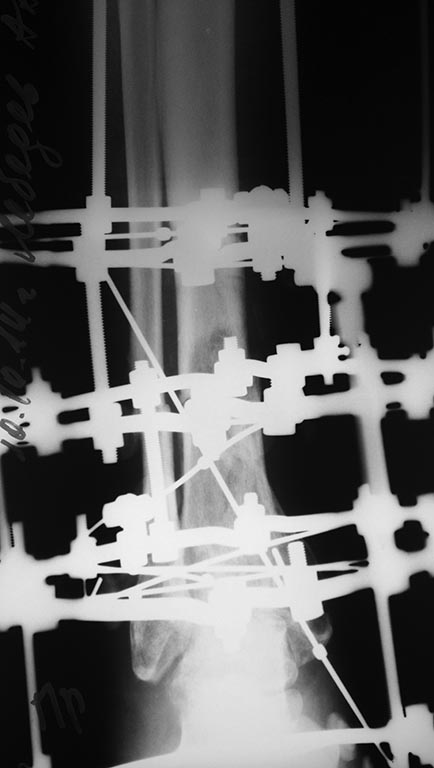

Небольшое уточнение: оперирован 1 августа, в ноябре снята база со стопы,

в конце декабря демонтаж аппарата. Показания к снятию аппарата-

заключение рентгенолога - консолидирующийся перелом, отсутствие

патологической подвижности. Рана заживала около 3 -х месяцев условно

первичным натяжением. Так как нет КТ руководствовались в основном

рентген снимками.

Снимки при поступлении, спустя 2,5 месяца. Рентген снимки после снятия

аппарата в архиве пришлю позже. Осылаю КТ от апреля.